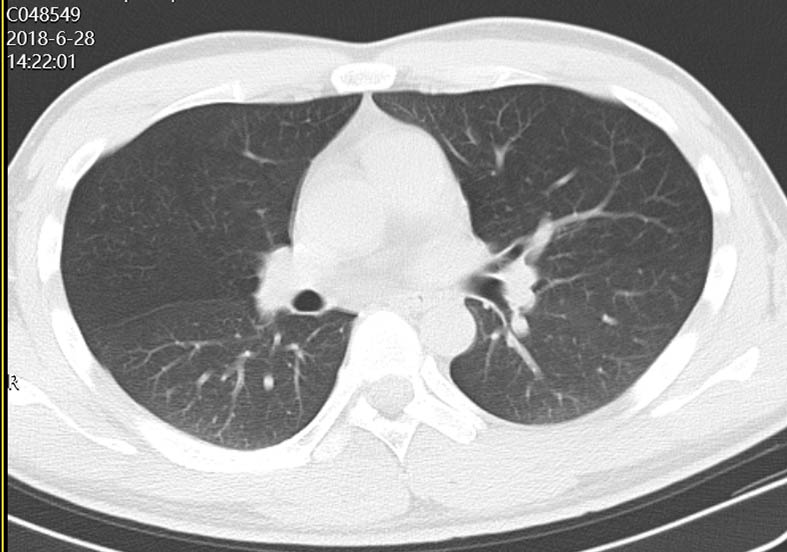

图 1 患者口服百草枯后胸部CT影像学变化

2018-06-28 CT图